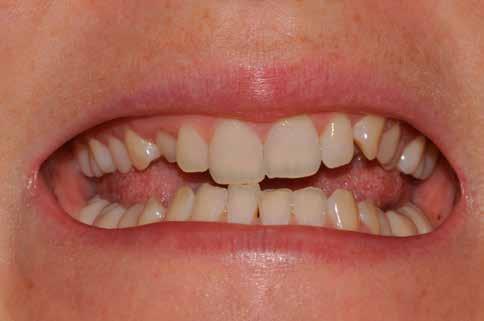

Hölgy páciensem az első konzultáció során tipikus kórtörténetet vázolt fel: Gyermekkora óta szeretett volna fogszabályozó készüléket, hiszen mindig is zavarta a class 2-es eltérésnél tipikusan jellemző nagy overjet (1-3. képek), és természetesen az ezáltal kifelé álló felső metszőfogai, részben a felső metszők protrúziója, részben pedig a disztálisan elhelyezkedő mandibula miatt. Annak ellenére, hogy több fogszabályozó szakorvosnál is járt az évek során, de mivel saggitális eltérése és az alsó metszőfogak torlódása miatt négy kisőrlőfog extrakcióját, illetve emellett sokszor állcsont műtétet is javasoltak neki, nem vágott bele a kezelésbe (4-5. képek).

A fogorvosa – nagyon helyesen – felhívta a figyelmét, hogy parodontális státusza is valószínűsíthetően romlani fog az eltérése miatt, újabb kört futott, immár 39 évesen, de még mindig premoláris fogak húzása és állcsontműtét nélkül szerette volna a fogszabályozást.

A konzultáció során arról is beszéltünk – ahogy az ilyenkor lenni szokott –, sohasem szeretett igazán mosolyogni, de a Pitts Protokolloknak köszönhetően az arc- és mosolyesztétikai céloknak megfelelően kerül megvalósításra az okklúziós korrekció. Az okklúziós kezelési célok az alábbiak voltak: a felső és alsó fogív nivellálása és tágítása, az alsó fogsor/ mandibula mezializálása, valamint a harapás megemelése által a mélyharapás rendezése.

A fogkontúrálás és az interproximális redukció alkalmazásával a mikroesztétikai részletek tökéletesítése is megtörtént (11. kép) A kezelés mindössze 16 hónapig tartott, megtörtént a rágófunkció helyreállítása, és az esztétikai végeredmény sokéves várakozás után valóban fordulópontot jelentett páciensünk életében (12-14. képek).